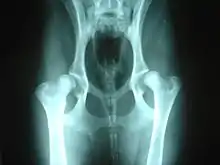

Hip dysplasia is diagnosed with radiographs of the pelvis. There are several standardized systems for categorising dysplasia, set out by reputable bodies. The most widely used systems include the following:

Radiographs can be sent to OFA for grading and certification.[11] This system rates a dog's hip joint on a seven-point scoring system. The test relies on interpretation of a radiograph of the dog's hips, which are then assigned a score by three independent radiologists: Excellent, Good, Fair, Borderline, Mild, Moderate and Severe.[12]